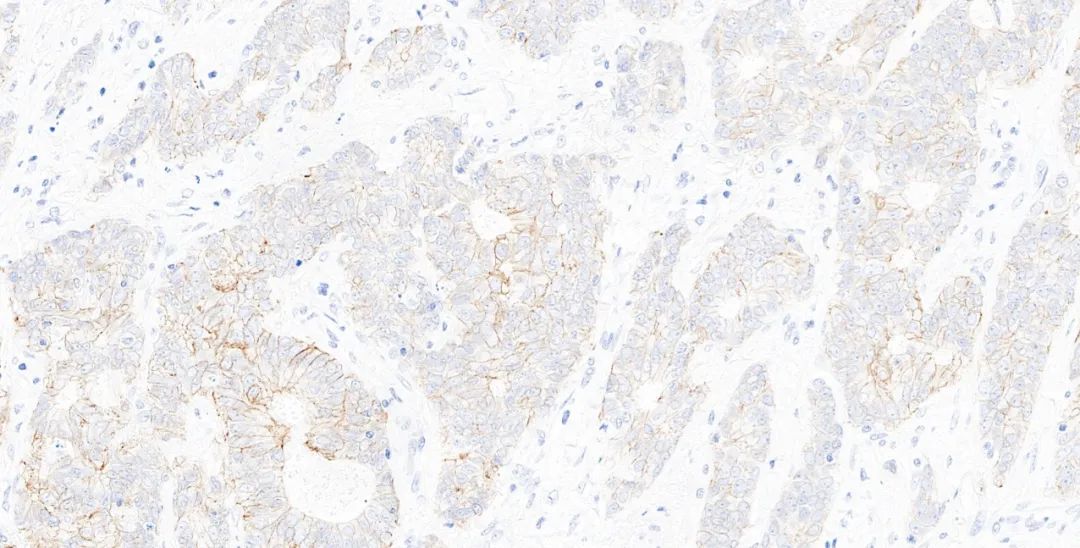

圖4.基因科技免疫組化測評結果圖:HER2(GT2245) 乳腺癌1-2+

384個實驗室參加了測試,獲得了82%(54%優異)的通過率,與最近的B32輪評估幾乎相同,與前三次評估B29-B31中的水平相比略有降低。結果不足的主要原因是假陰性結果或信噪比差,影響了讀數。